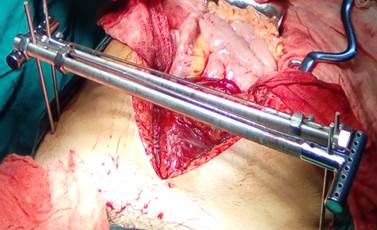

Dada la persistencia de la inestabilidad hemodinámica se decidió la intervención quirúrgica urgente, mediante fijación externa a través de dos alambres de Steinman de 3,5 milímetros roscados percutáneos a nivel de cada cresta ilíaca, conectados a cada cresta por una barra en T del fijador RALCA ® (Rodrigo Álvarez Cambras) y estas a su vez se interconectaron a través de dos pistones, lo cual conformó un marco rígido (Figura 2).